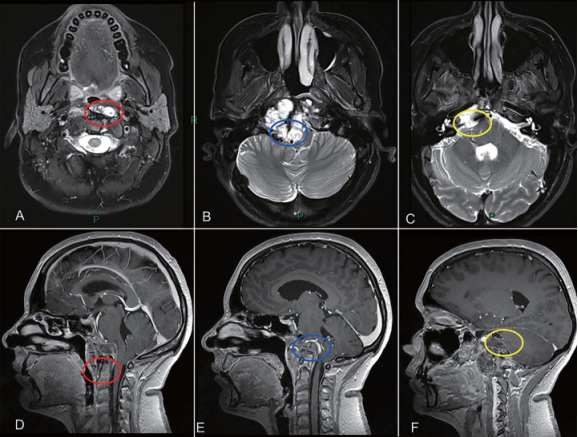

图2:颅颈交界区肿瘤手术治疗策略分析,肿瘤的旁正中部分可以通过经鼻内镜手术切除。枢椎齿状突周边肿瘤(A和D处红色圆圈)、侵犯硬膜内部分的肿瘤与后循环接触(B和E处蓝色圆圈)和先前乙状窦后入路手术的粘连(C和F处黄色圆圈),这些部位的肿瘤更适合第二期远外侧开颅手术。